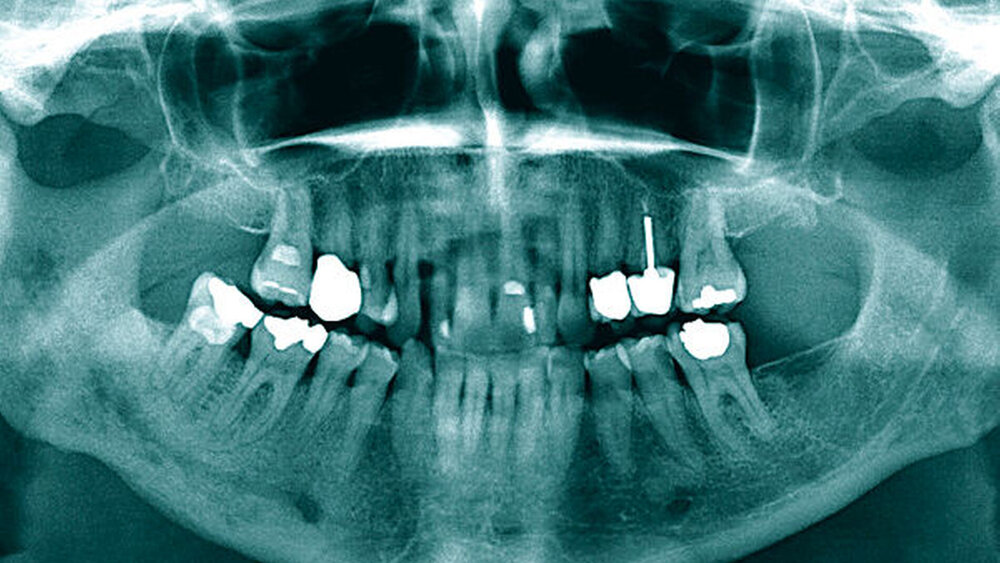

Im Rahmen der Fokussuche erfolgte neben der Anfertigung eines Orthopantomogramms (Abbildung 1) die Durchführung einer Computertomografie (Abbildung 2). Der röntgenologische Befund dokumentierte osteomyelitisch typische CT-morphologische Korrelate wie eine inhomogene großflächige Sklerosierung des rechten Unterkiefers mit zystisch-osteolytischen Veränderungen. Bei klinisch und radiologisch dringendem Verdacht auf eine primär chronische Osteomyelitis des Unterkiefers wurde nach Erörterung der Therapiemöglichkeiten mit der Patientin die Indikation zur zeitnahen operativen Intervention gestellt.